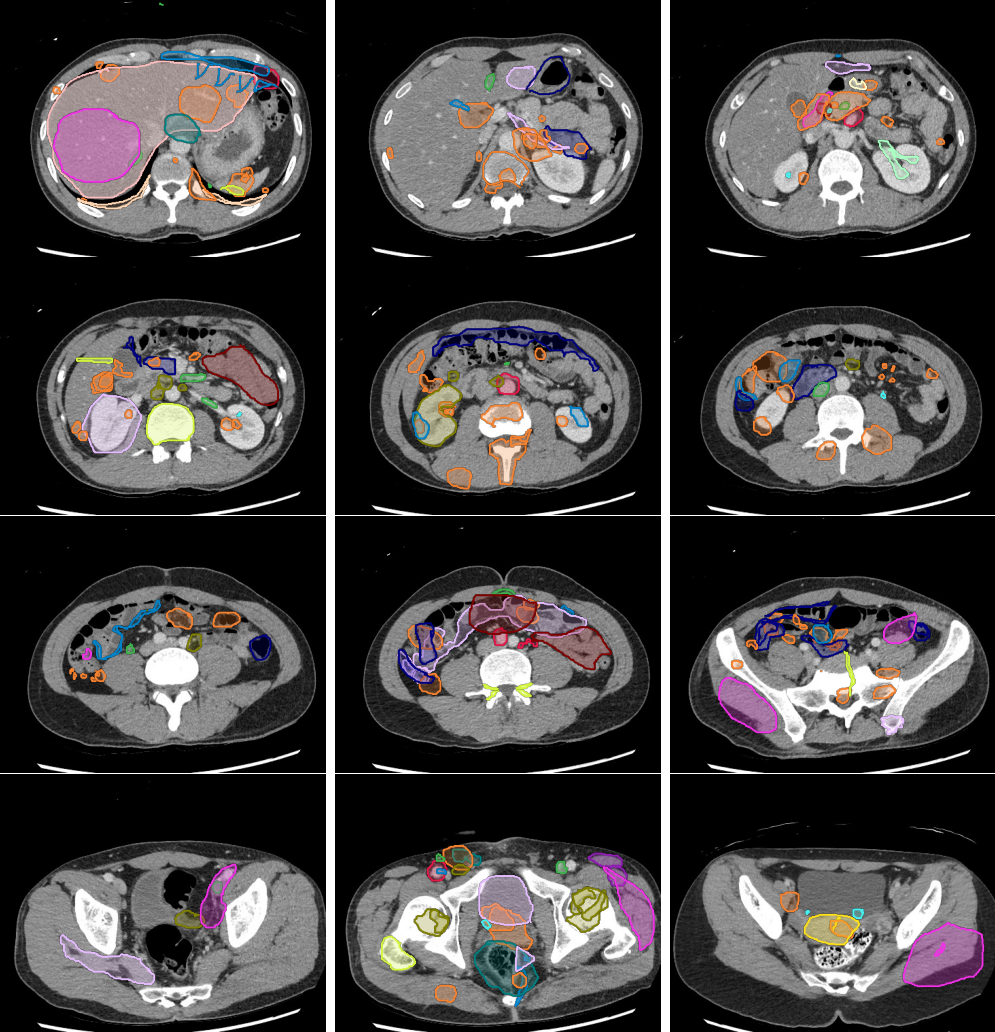

Abnormal Air

Mass or Adenopathy

Avascular Necrosis

Devices

Fistulas

Fracture

Hemorrhage

Hernia

Infection or Inflammation

Laceration

Obstruction

Stones

Thrombus

Other Vascular

Legend

Slice 1

Slice 2

Slice 3

Slice 4

Slice 5

Slice 6

Slice 7

Slice 8

Slice 9

Slice 10

Slice 11

Slice 12